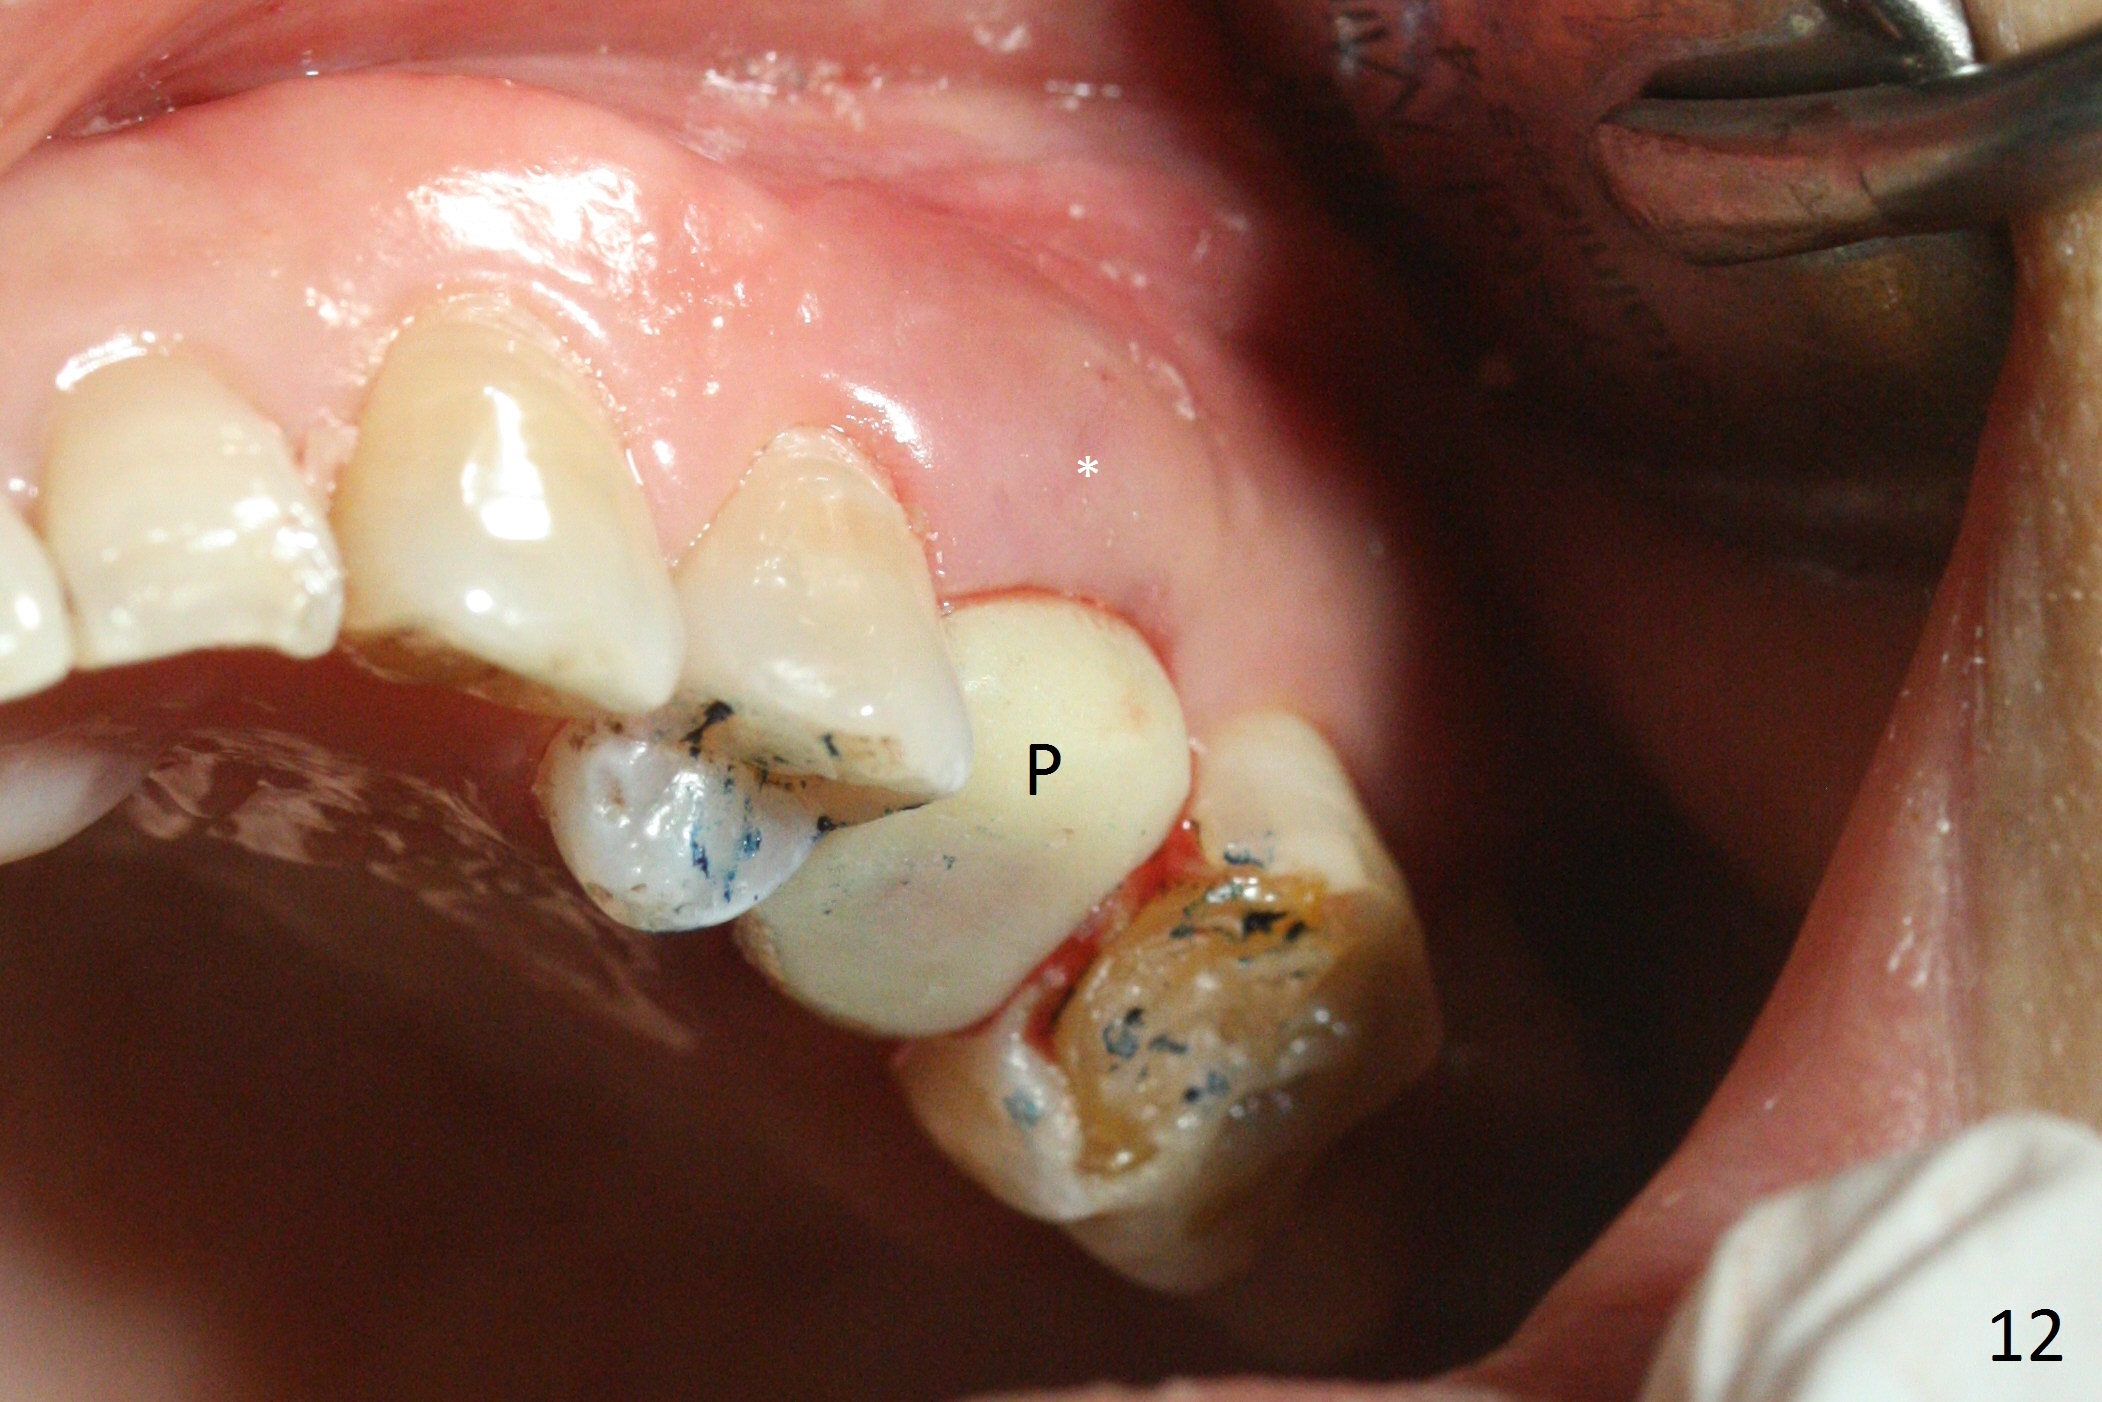

The buccal gingiva over the tooth #13 (Fig.1 white *) with crack (Fig.2 (mesial view of the extracted tooth)) is erythematous with deep buccal (B) pockets, which do not appear to extend the level of exostosis of the neighboring teeth (Fig.1 black *), i.e., coronal to the apical end of the crack with granulation tissue (Fig.2 *). Osteotomy is initiated with a 1.6 mm drill in the palatal aspect of the socket (Fig.3) so that an implant will be placed palatal (Fig.8,11) and there is enough buccal gap for bone graft (Fig.8 *). After withdrawal of 3.3 mm Magic Drill (trephine bur), the osteotomy (Fig.4 O) plug (red outline) is intentionally left in situ. When a 4x11 mm dummy implant is placed (Fig.5 (green outline), 6), the plug is compressed (Fig.5). With placement of a definitive implant (4.5x13 mm, Fig.7 (green), 9), the plug as well as the sinus floor (Fig.4 SF) is lifted (Fig.7 red curved line), 9 (arrowheads)). In brief the autogenous bone is used for sinus lift. There is no intra- or post-op nasal hemorrhage. With a small piece of gauze (Fig.8 G) in the implant well, allograft is placed in the buccal (mainly) and palatal gaps until the level of the implant plateau. Then a 4.5x4(3) mm abutment is placed (Fig.9-10 A). Next another piece of gauze is placed in the space corresponding to the abutment cuff (Fig.11 G) for fabrication of an immediate provisional (Fig.12 P). More bone graft is placed in the soft tissue zone (dual zone technique) after gauze removal and before provisional seating. With dual zone bone graft technique and provisional support, the soft tissue atrophy should be expected to be minimal (Fig.12 *). The zone of exostosis (more coronal) should be much less, since the bone density in the zone is high.